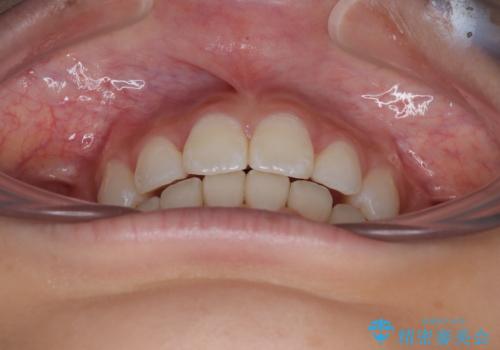

斜め前に飛び出した前歯 抜歯矯正で素敵な横顔に

- 口を閉じたときに飛び出してしまう上顎前歯を気にして来院された患者様です。

下唇に前歯が当たって跡が残ってしまう状態でしたが、スッキリとした口元に仕上げることができました。